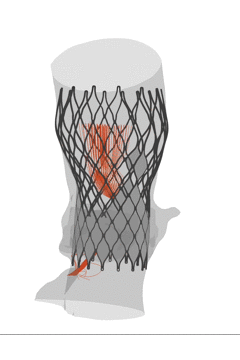

FEops评估瓣膜释放稳定性

根据FEops评估报告得知,选用L29瓣膜的高位释放与标准位释放,最终稳定位置与初始位置差异较大,评估瓣膜在这两个位置释放发生移位风险比较大,建议使用A+减小手术风险。

L29号瓣膜标准位植入后的稳定形态

* 根据FEops评估报告,瓣膜释放之后的稳定位置与初始释放位置差异较大,且患者伴有风湿性心脏病,综合评估该患者发生瓣膜移位风险比较大;